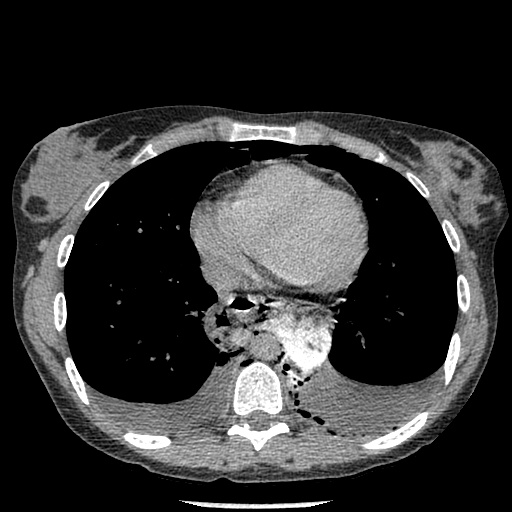

A subsequent scan revealed a small amount of contrast extravasting from the esophagus into the mediastinum.

Figure 3: CT of the chest confirming pneumomediastinum and showing focal extravasation of contrast from the esophagus into the mediastinum.

I discussed the case with the ER physician. The clinical and imaging findings pointed to a diagnosis of Boerhaave’s Syndrome, a syndrome consisting of rupture of the esophageal wall due to vomiting.

The condition is associated with a high morbidity and mortality and is fatal in the absence of surgical therapy. The somewhat nonspecific nature of the symptoms of the syndrome, however, have sometimes been described to contribute to a delay in diagnosis. The patient was transferred to tertiary surgical centre within an hour of her chest x ray.